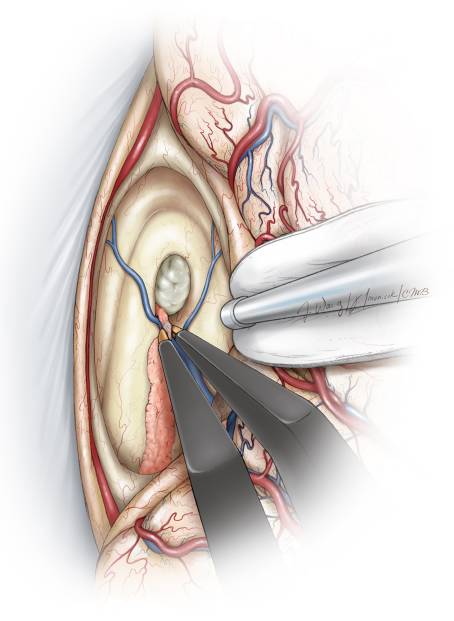

图13. 在笔者减压肿瘤之前,始终以脑室壁为参照以避免在减压操作时穿透肿瘤包膜。笔者首先将肿瘤包膜从脑室顶壁游离(左上图)。然后,采用超声刀进一步减压并将囊壁从脑室外壁上分离(右上图),重复这些步骤直到囊壁从脑室底锐性分离(下图)。如果肿瘤侵入三脑室底部软膜,通常会在切除肿瘤后的空腔底部发现视神经和视交叉(Redrawn from Tew, van Loveren, Keller*)。

总之,切除肿瘤首先从内减压开始,然后切除前方、外侧、后方,最后沿囊壁下方分离切除。